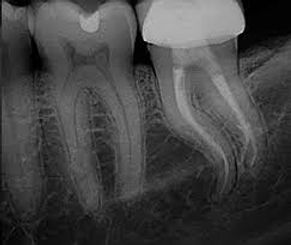

Kanal kalsifikasyonu; dişin içindeki pulpa dokusunun zamanla sertleşmesi ve kök kanallarının daralması veya tamamen kapanması durumudur. Normalde röntgende net şekilde görülebilen kanal boşlukları, kalsifikasyon geliştiğinde belirsizleşir veya tamamen görünmez hale gelir. Bu durum, çoğu zaman belirti vermeden ilerler ve genellikle rutin radyografik kontroller sırasında fark edilir.

Belirti olmasa bile, kalsifikasyon sadece radyografide görülebilir ve düzenli hekim kontrolü gerektirir.

Kanal Kalsifikasyonu Tedavi Edilir mi?

Kalsifiye kanallar teknik olarak daha zor olsa da günümüz endodonti yöntemleriyle tedavi edilebilir. Uygun büyütme sistemleri, mikroskop ve modern enstrümantasyon teknikleri ile bu tür kanalların açılması ve temizlenmesi mümkündür.